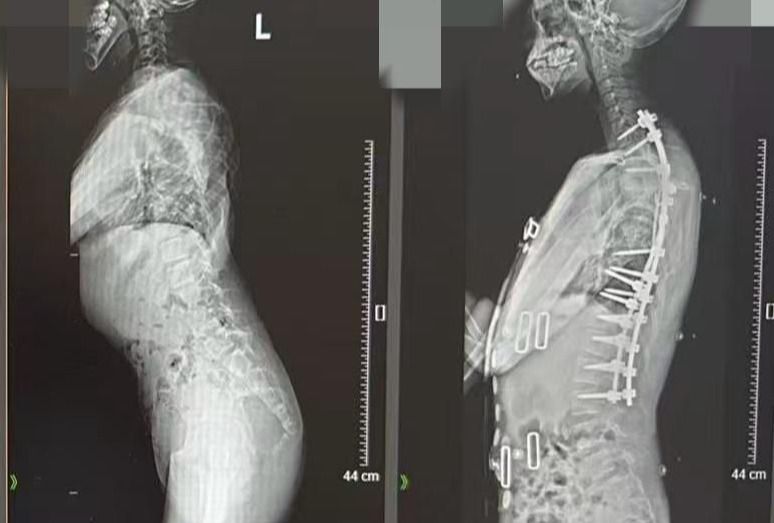

脊柱侧弯150°的少年,第一次挺直了脊背

2月28日,国际罕见病日来临之际,在南方医科大学第三附属医院脊柱外科的病房里,少年阿文(化名)正与医护人员轻松交谈,眼神清亮,脊背挺直。